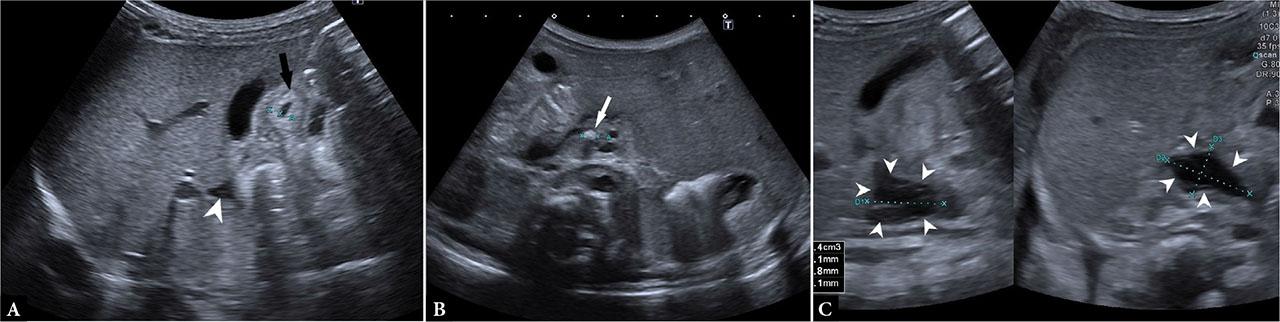

A post-term female neonate was admitted to the neonatal ward due to neonatal hypoxic-ischemic encephalopathy. During her hospital stay, routine abdominal US showed a cluster of small gallstones within the gallbladder, without signs of cholestasis or inflammation. At nine days of age, she was discharged home. She was readmitted three days later due to vomiting, refusal to feed, and elevated gamma-GT and bile acids. Repeated abdominal US showed a variably sized gallbladder free of stones, a normal-sized main bile duct with a small hyperechoic focus in its distal portion, suspicious for a small stone, an adjacent fluid collection, and a thickened duodenal wall (Fig. 1).

Ultrasound findings suggestive of biliary perforation in the first patient: A. normal gallbladder wall thickness without intraluminal stones, thickened hyperechoic duodenal wall (black arrow) and a pouch of fluid collection (arrowheads), B. small hyperechoic formation with distal shadowing at the end of the common duct suspicious for a small stone (arrow), no bile duct dilatation, c) localized fluid collection (arrowheads)